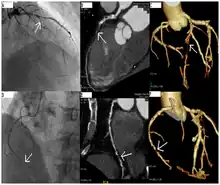

Alternative approaches

CT angiography can act as a less invasive alternative to Catheter angiography. Instead of a catheter being inserted into a vein or artery, CT angiography involves only the injection of a CT-visible dye into the arm or hand via an IV line. CT angiography lowers the risk of arterial perforation and catheter site infection. It provides 3D images that can be studied on computer, and also allows measurement of heart ventricle size. Infarct area and arterial calcium can also be observed (however those require a somewhat higher radiation exposure). That said, one advantage retained by Catheter angiography is the ability of the physician to perform procedure such as balloon angioplasty or insertion of a stent to improve blood flow to the artery.[7]